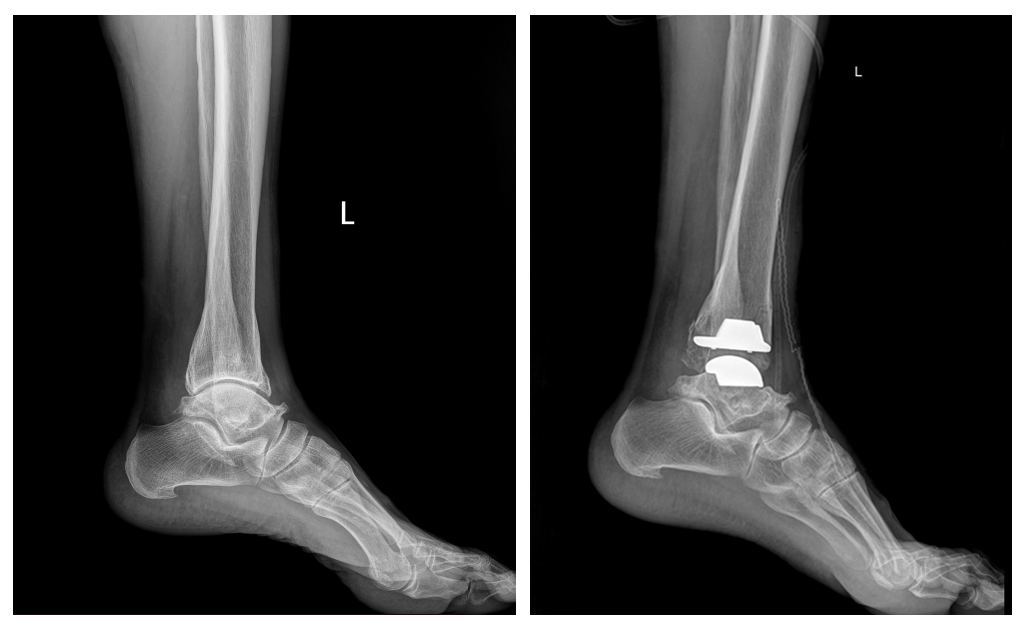

ГССҮТөвийн Насанд хүрэгсдийн гэмтэл согогийн тасгийн их эмч Г.Бадамгарав, Ш.Баасансүрэн, Ц.Батбаяр нараар ахлуулсан мэс заслын баг хамт олон БНСУ-ын Йонсей Гунвоо эмнэлгийн захирал Eui Hyun Park болон эмч мэргэжилтнүүдтэй хамтран ЭХ ОРОНДОО АНХ УДАА шагайн үений хүнд хэлбэрийн артроз өөрчлөлтийн үед ХИЙМЭЛ ҮЕ СУУЛГАХ мэс засал эмчилгээг амжилттай нэвтрүүллээ.

Энэхүү орчин үеийн дэвшилтэт мэс засал эмчилгээг өөрийн оронд нутагшуулснаар шагайн үений артрозоор шаналж буй олон хүмүүст өвдөлт зовууриасаа салах, амьдралын чанарыг сайжруулах бас нэг боломжийг олгож байгаа юм.